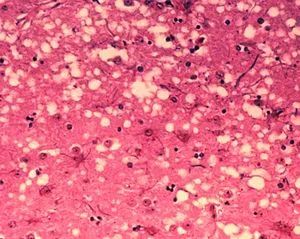

被朊毒體(ti) 感染的腦組織產(chan) 生了海綿狀空洞 圖片來源:wikipedia